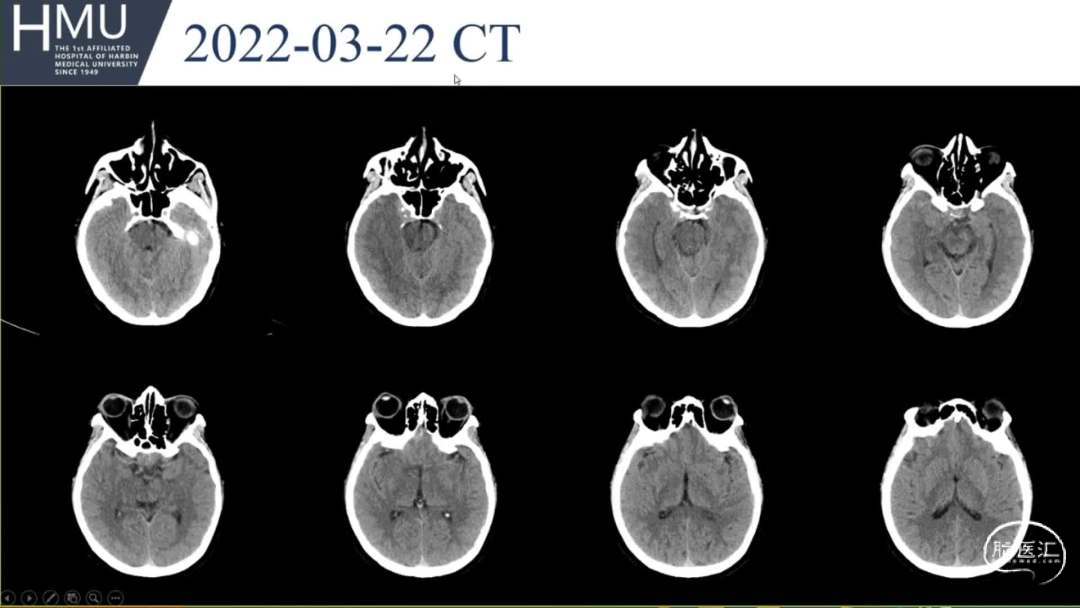

23日06:00

患者答非所问,查体不配合

急行头部CT

23日14:00患者刺痛不睁眼,不发声,

右上肢刺痛定位,左侧瞳孔光反射消失。

16:00急诊行钻孔引流术